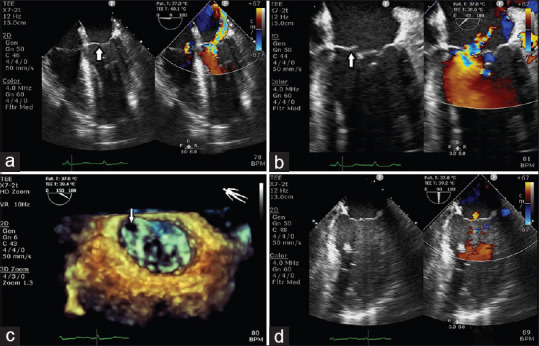

Acute Mitral Regurgitation Following Minimally Invasive Aortic Valve Replacement.

微创主动脉瓣置换术后急性二尖瓣返流。